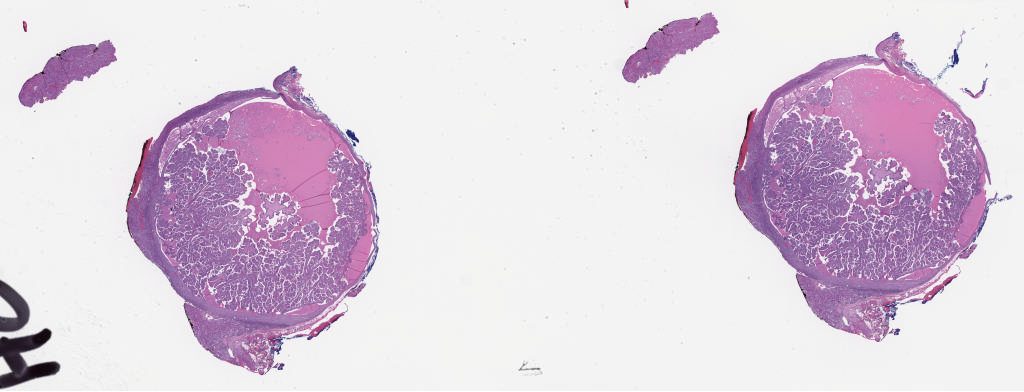

548237.svs

40X